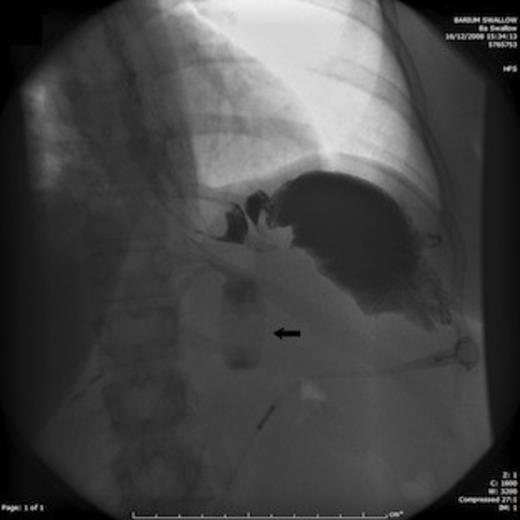

A Barium swallow study, performed on the fifth day post-operation was reported, initially by a senior radiologist, as not showing evidence of mechanical obstruction. However, due to the patient's continued deterioration, we suspected mechanical obstruction after reviewing the barium swallow, so we sought a second opinion from the radiology department, who confirmed this (Figure 1). Therefore, a decision to proceed with an urgent laparotomy that was performed that afternoon.

Barium swallow showing signs of mechanical obstruction with no contrast seen beyond the fundus of the stomach. The arrow demonstrates the gastric band, which was found behind the stomach acting as an axis for gastric torsion

Intra-operatively, the gastric band was found in adhesion posterior to the stomach, and was removed. The stomach, which was found torted at 180 degrees, remained viable and was therefore not resected.